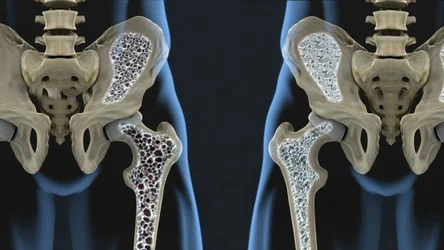

Иллюстрации и снимки, связанные с остеопенией шейки бедра